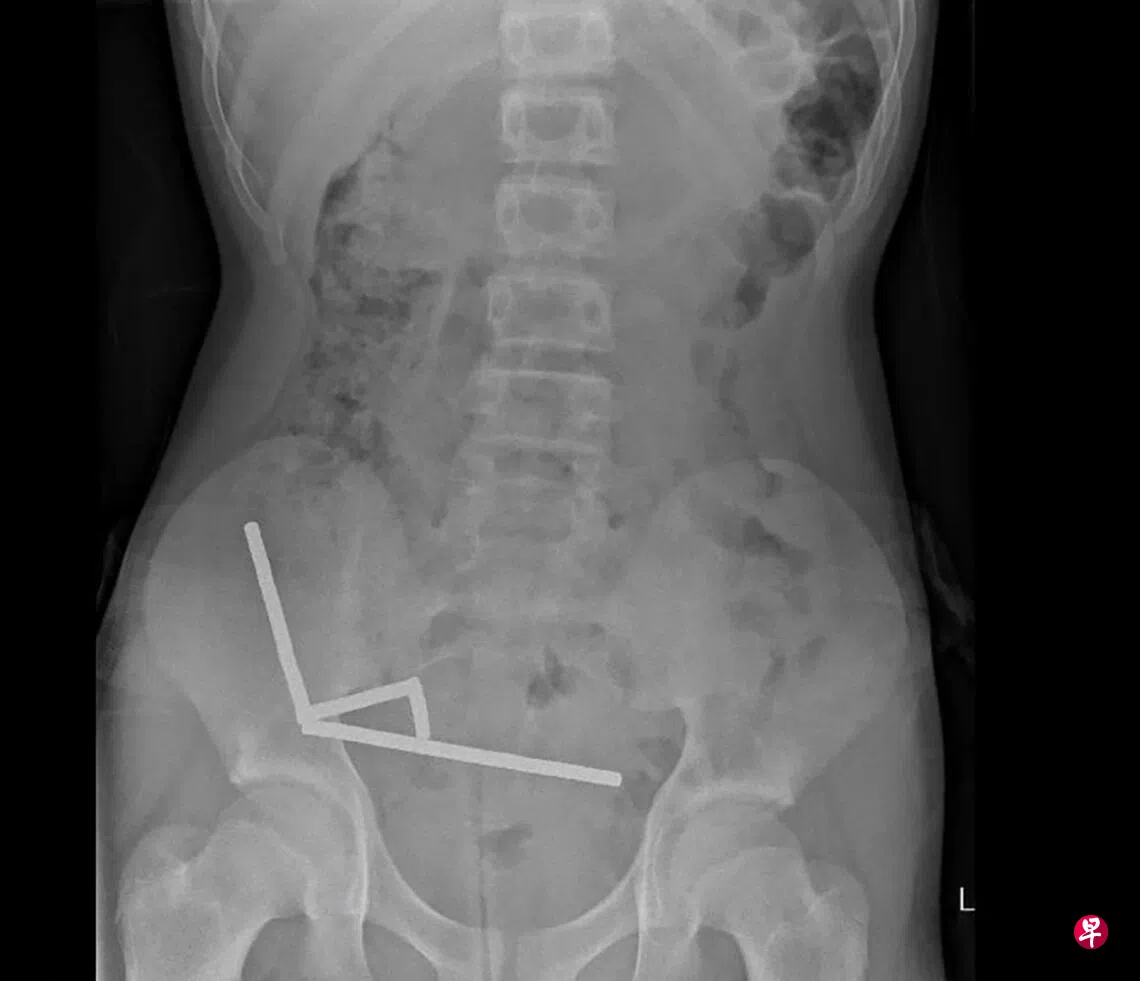

新西兰一名13岁少年吞下80至100片微小但磁力超强的钕铁硼磁铁,在肠道连成四条直线,导致小肠和盲肠四处组织坏死,须紧急动手术取出磁铁及切除坏死组织。